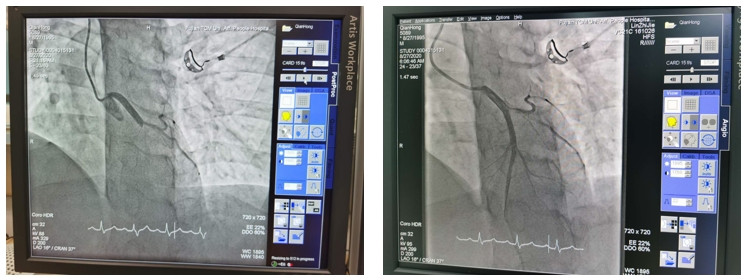

急性心肌梗死急诊介入

急性心肌梗死急诊介入血栓抽吸术